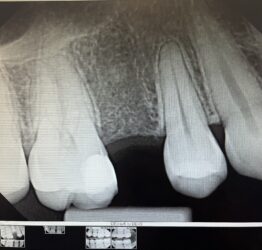

I have been placing Implant club implants for the past 2-3 years (yes Ivan, I know you that much), and my beautiful GF needed an implant. Extraction and bone grafting was performed. Today I did the uncover. 60% of my cases, I have notice this overgrowth of bone. This on was part of the statistics. I just wanted to show off/share the case.